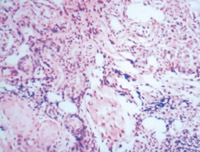

5-2-3 伤后第3天,表皮细胞空泡化,真皮浅层胶原纤维玻璃样变,真皮内散在炎细胞浸润 HE×100